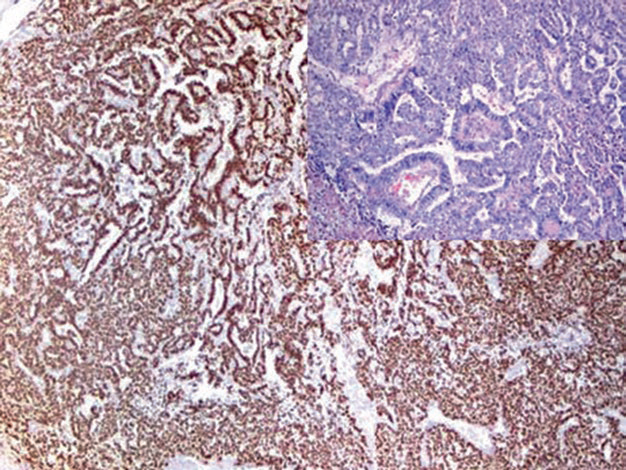

Figure 1. Strong nuclear expression of SALL-4 in yolk sac tumor.